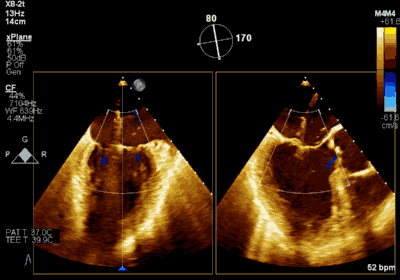

▲ 术前超声检查显示重度二尖瓣反流

▲ 术后超声检查显示轻度二尖瓣反流